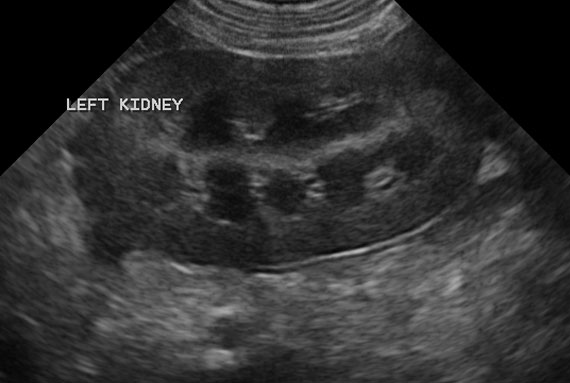

Ultrasound

Dr Irene has done many courses on Ultrasound and has vast experience. She also visits other vet practices to do their ultrasounds.